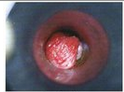

痔疮有很多的种类,有内痔外痔以及混合痔,肛门脱垂等等,还有其他的种类,小编知识不全,欢迎补充,下面来说说微创切除术的5大优点